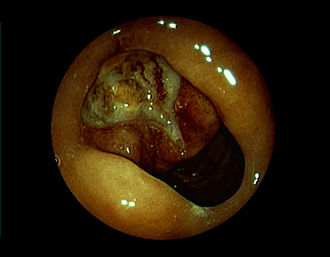

症例3:十二指腸潰瘍(53才男性)

1年前からの慢性胃痛を主訴に当院受診。十二指腸球部前壁に深くて大きな潰瘍(Stage A1)があり、潰瘍底は厚い白苔に覆われ、一部白苔のはみ出しを認める。潰瘍周囲粘膜は浮腫を伴っている。ボノプラザンフマル酸塩投薬で治療開始しました。